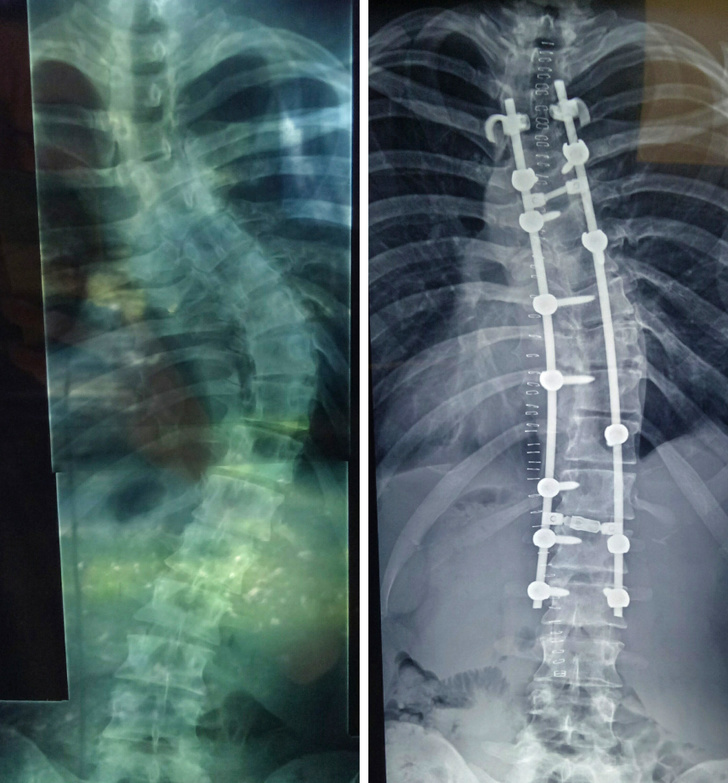

▼4.「我再也不會感到痛苦了。雖然還是無法很自在地移動身體,但是這個決定做對了。」

▼15.「這是我終於可以再次做單槓時的心情!因為做了背脊手術不得不休養,好不容易等到終於能夠再次運動,真的很爽啊!」